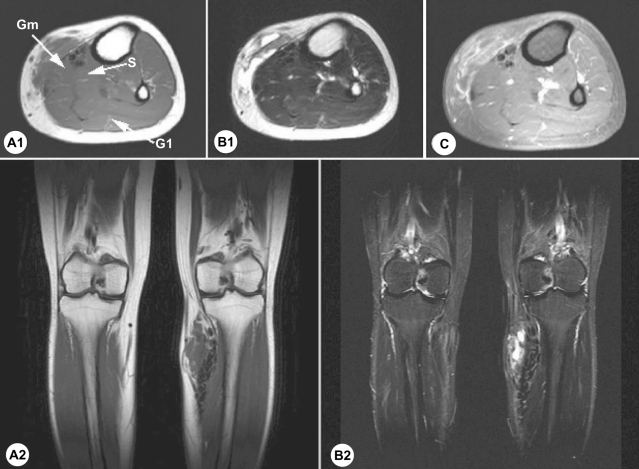

On physical examination, relatively ill defined, variously sized, round or elongated, soft nodules were detected on the medial aspect of her left leg and popliteal fossa. Routine laboratory test results were within reference ranges, and no leukocytosis and no eosinophilia was detected in the peripheral blood. A plain knee radiograph taken at a primary clinic demonstrated multiple discoid calcifications around her knee (Fig. 1). Ultrasonography revealed subcutaneous hypoechoic elongated nodules and irregular intramuscular calcifications in the left lower leg antero-medially with slightly increased peripheral vascularity. Elongated and dilated superficial veins were also identified along the hypoechoic nodule and this showed compressibility at the same time (Fig. 2). Magnetic resonance (MR) imaging revealed a multilocular (tubular and round) subcutaneous lesion (width 45 mm, thickness 15 mm, length 75 mm) in the antero-medial aspect of the proximal left lower leg. The lesion showed low signal intensity on T1 weighted images, high and low signal intensities on T2 weighted images, and irregular thick rim enhancement. Numerous calcific foci were noted along the medial margin of the soleus and medial head of the gastrocnemius muscle. Sporadic intra- and intermuscular calcific foci were also noted at the postero-lateral portion of the distal thigh, which showed faint rim enhancement (Fig. 3). The preoperative diagnosis was made as a partly thrombosed varicose vein associated with myositis at adjacent muscles.

On plain radiographs, calcification has been reported as an important diagnostic clue of cerebral sparganosis (Chang et al., 1992; Dunn and Palmer, 1998). The sonographic findings include a linear echogenicity with a 'dot and dash' pattern in some portion of the tract, which is a highly characteristic finding of sparganosis (Cho et al., 2002). Our patient also disclosed similar findings, but dilated veins along and around mass with compressibility on ultrasonography made us confusing the diagnosis. The live sparganum, with an overlying soft capsule, was misinterpreted as a partly thrombosed varicose vein. MR images of muscular sparganosis are conglomerated cystic lesions and reactive changes in the adjacent soft tissues. The imaging appearance of the cystic lesions with surrounding reactive changes may resemble pyogenic infections, other parasitic infections (cysticercosis and paragonimiasis) or hemangioma, and these must be differentiated. Moreover, if serpiginous tubular tracts are observed during imaging studies, musculoskeletal sparganosis should be included in the differential diagnosis (Cho et al., 2002). Laminated calcospherules in the cytoplasm of proliferating macrophages and giant cells are of diagnostic value if no sparganum worm is present in a lesion (Chi, 1980).